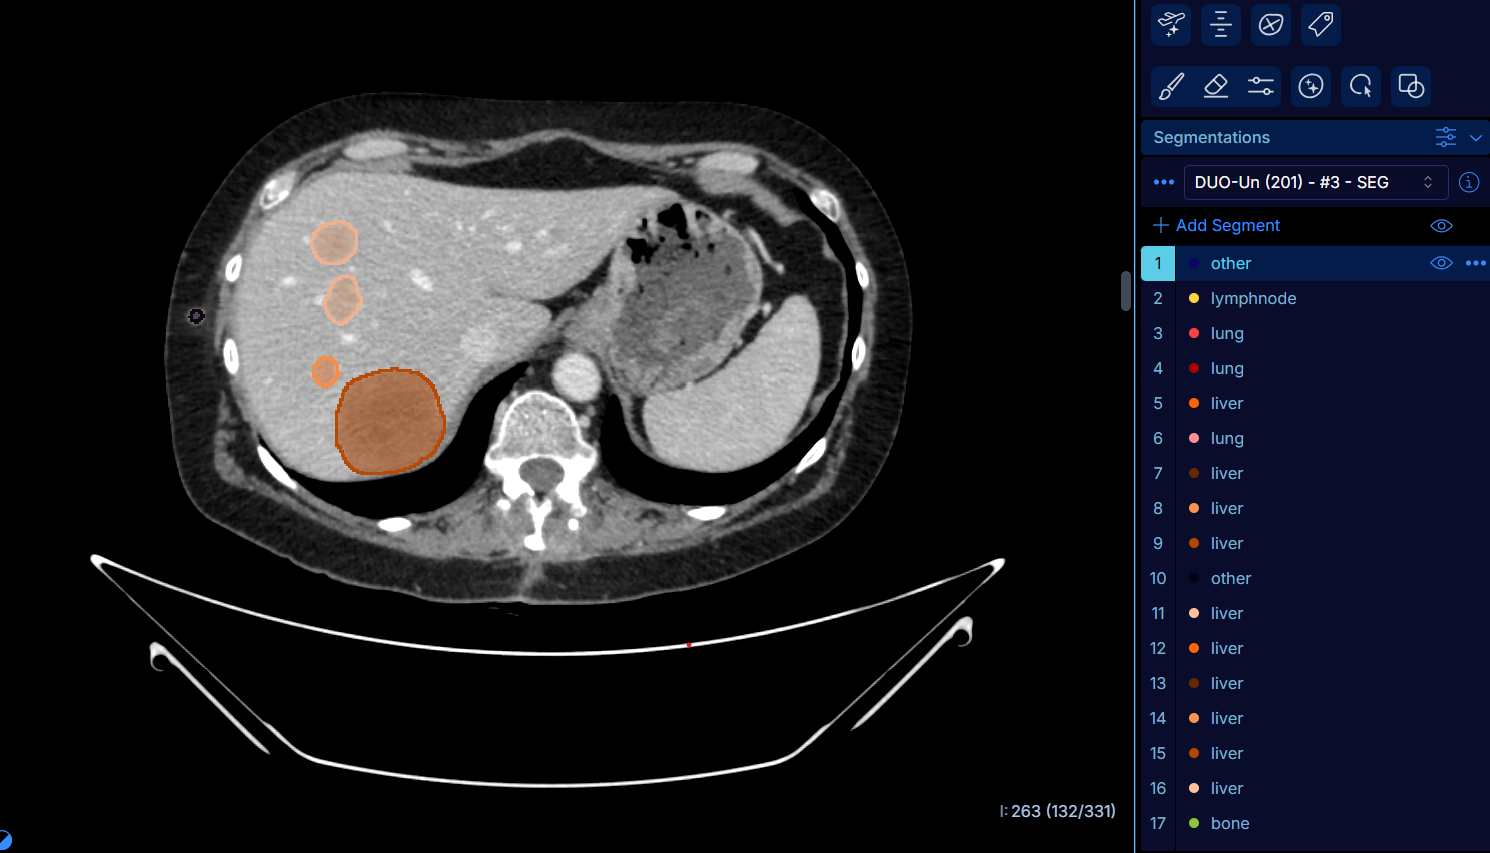

Pour répondre à cet enjeu, Gustave Roussy a participé au développement d’un outil d’intelligence artificielle capable de mesurer la charge tumorale des patients à partir d’un examen d’imagerie, dans le cadre d’un consortium composé de Guerbet, d’Intrasense et du CHU d’Angers, avec le soutien de BPI France et du programme France 2030. Cet outil, baptisé DuOnco Unity, repose sur un algorithme d’IA à même de détecter automatiquement et en trois dimensions l’ensemble des tumeurs et des métastases visibles sur un scanner thoraco-abdomino-pelvien. Cette analyse permet de mesurer la charge tumorale réelle des patients dans cette zone et de générer des indicateurs pour prédire l’évolution de la maladie.

DuOnco Unity, à la fois multi-organes et multi-anatomique, est un outil unique au monde. Il fonctionne sur l’ensemble du thorax, de l’abdomen et du pelvis, et est également capable d’analyser les ganglions lymphatiques, une fonctionnalité rare et particulièrement utile puisqu’ils représentent l’un des principaux sites métastatiques. Enfin, il intègre la masse musculaire et les tissus adipeux dans ses comptes rendus, des indicateurs importants pour établir un diagnostic précis en oncologie.

Le développement de cet outil a nécessité l’annotation de près de 287 000 lésions afin d’entraîner l’algorithme. Il a été pensé pour s’intégrer le plus naturellement possible dans l’univers de travail des radiologues, avec une interface simple pour faciliter son déploiement et son adoption en France et à l’étranger. Les données sont hébergées localement afin d’éviter leur export vers des serveurs extérieurs.